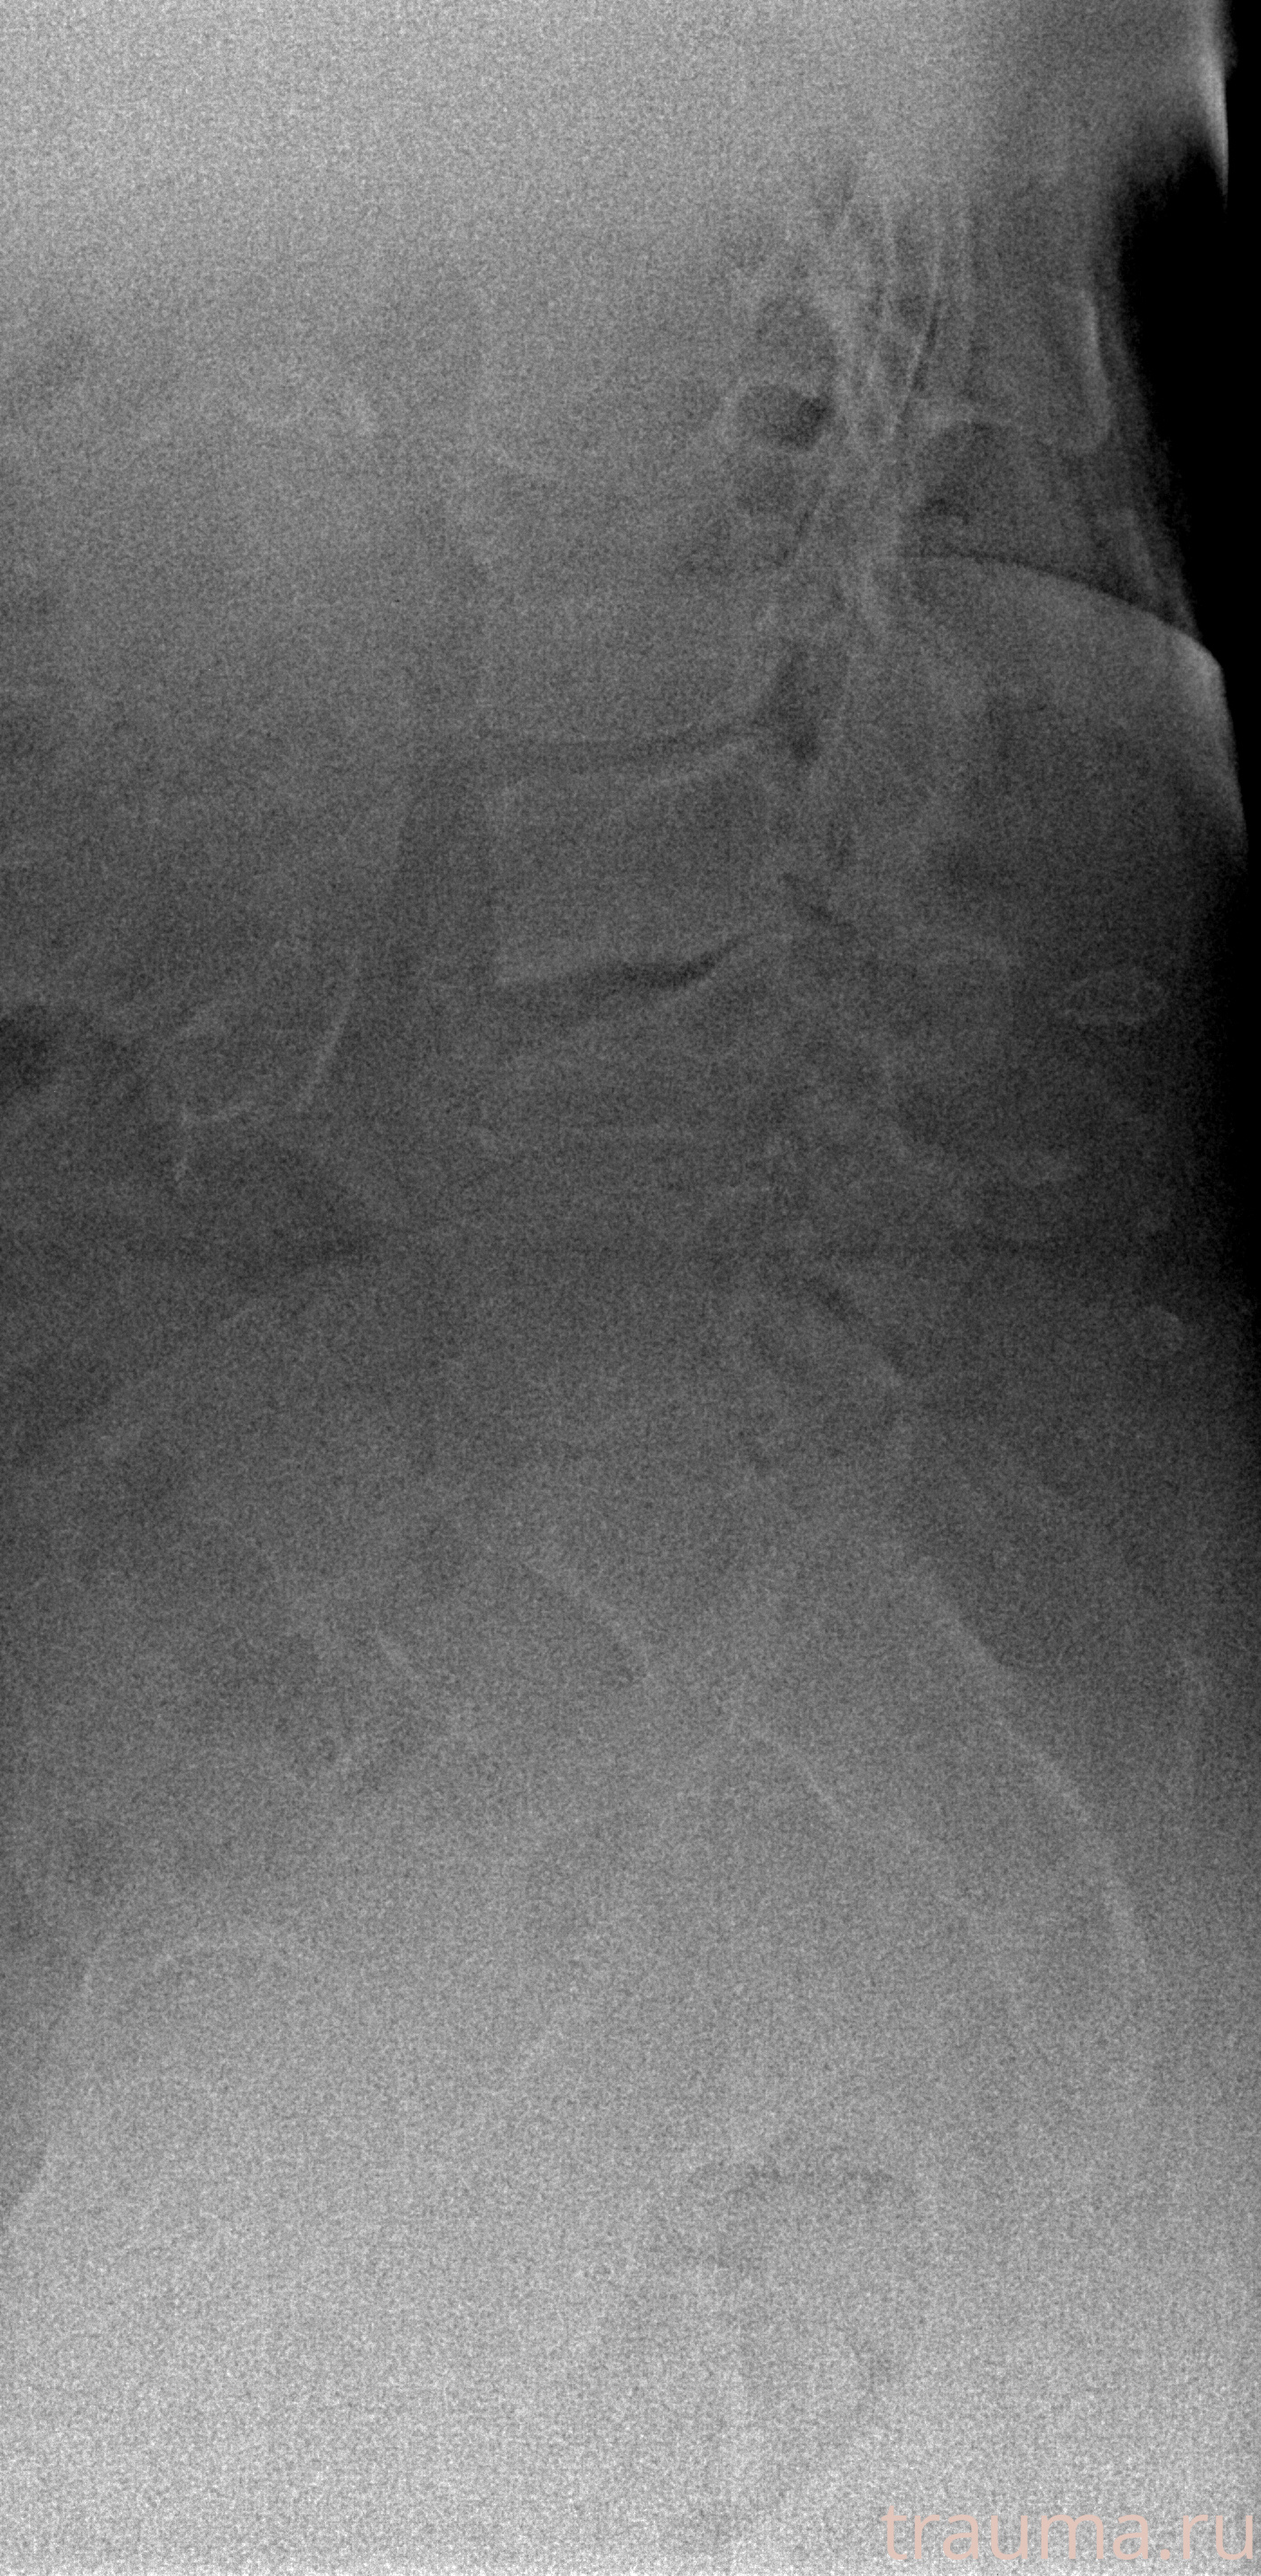

Рентгенограммы

Рентген на дому: по вашему адресу приезжает врач-рентгенолог, травматолог-ортопед с мобильным рентгеновским аппаратом, проводит диагностику травмы или заболевания, делает необходимые рентгенограммы, дает рекомендации по дальнейшему лечению. Получить качественные снимки в домашних условиях возможно благодаря уникальной методике, разработанной МосРентген Центром для института  Склифосовского